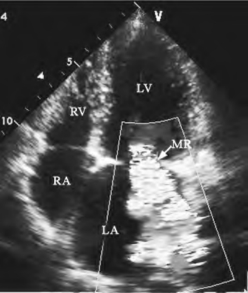

①左房异常反流束:收缩期以蓝色为主的五彩镶嵌反流束由左室经二尖瓣对合不良间隙处(图13-8)或穿孔、撕裂部位进入左房。

②反流束形态:反流起始部直径较窄与反流口直径相近,进入左房腔后扩散,反流束形态多数呈束状或喷泉状。

③反流束方向:多数指向左心房中部或后侧壁,少数沿二尖瓣环、左房壁或房间隔走行至左房后壁或上壁,发生方向转折,形成环形反流束。

图13-8 二尖瓣反流(MR)二维彩色多普勒图(见彩图11)

④反流束止点:反流束多数止于心房腔中,少数可止于左房边缘或心房顶部。